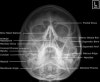

(1) 안면부 손상의 일반적인 촬영은 Occipitomental 또는 Occipitomental 30º 영상이다.

3) Adult Facial Bones - Occipitomental(Waters) 30º View